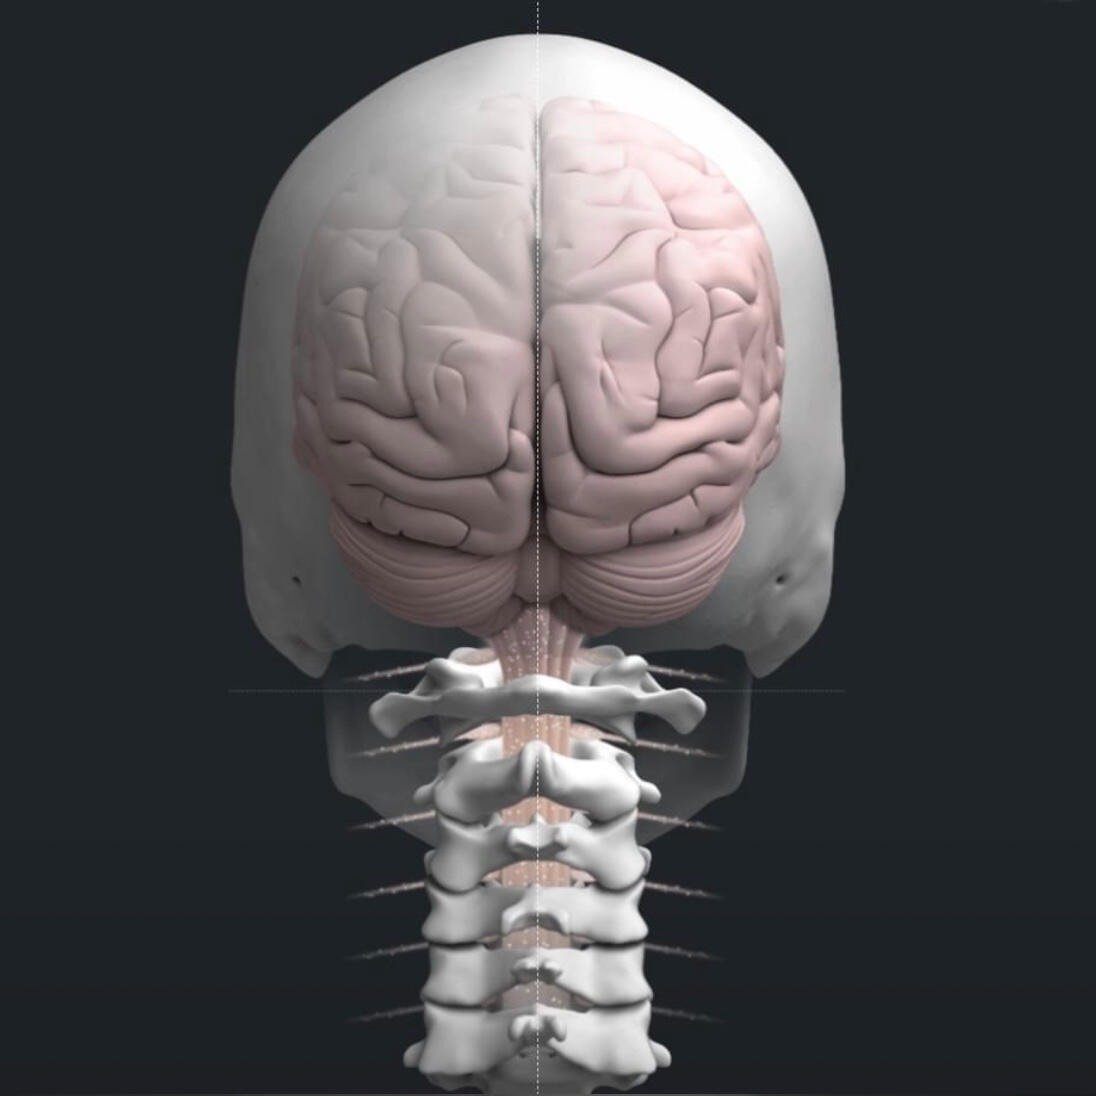

Our chiropractic care focuses on how the brain and nervous system communicate with the body. We use precise, specific adjustments, not force, to support function and healthy adaptation.This approach is gentle and safe for families, children, and athletes alike. The goal is not chasing symptoms, but helping the body change how it adapts and functions over time.